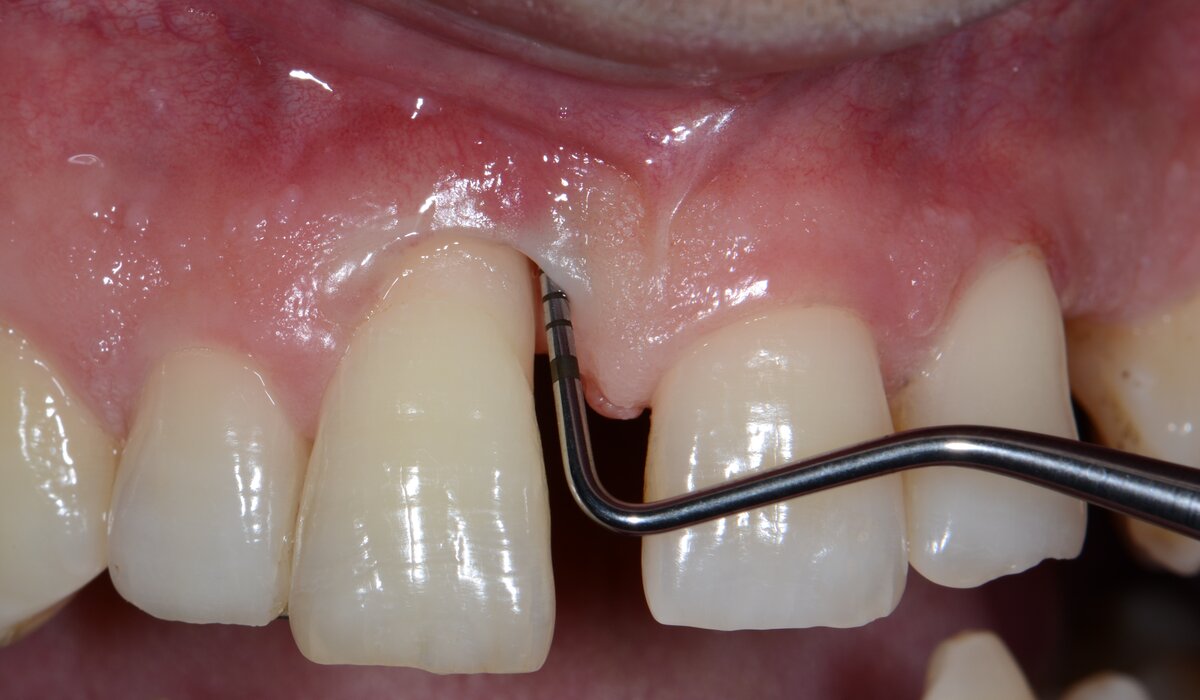

Papilla height, the stability of the buccal gingival margin, and the prevention of post-surgical recession are critical. Also, in the presence of thin periodontal tissues, there is a higher risk of soft-tissue collapse and flap shrinkage.

For these reasons, incision design and soft-tissue management must be executed with the utmost conservatism to preserve tissue integrity and optimize clinical outcomes. Conversely, in the posterior maxilla, aesthetic demands are generally lower and the soft tissue is often thicker, which allows the use of more conventional flap designs. Minor recessions or volume changes are usually well tolerated.

Surgical techniques should prioritize the achievement and maintenance of primary wound closure. In this context, papilla-preservation approaches have been advocated to maintain soft-tissue integrity and optimize regenerative outcomes. These techniques offer several advantages, including enhanced aesthetic preservation, improved wound stability, and compatibility with a wide range of regenerative biomaterials.

Nevertheless, they are inherently technique-sensitive. In situations with narrow interdental spaces, the restricted access may hinder tissue manipulation and require meticulous suturing to ensure stable primary closure.